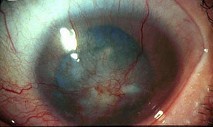

(如图)该种疾病的病因可能是由于()

-

(如图)该疾病的说法正确的是()